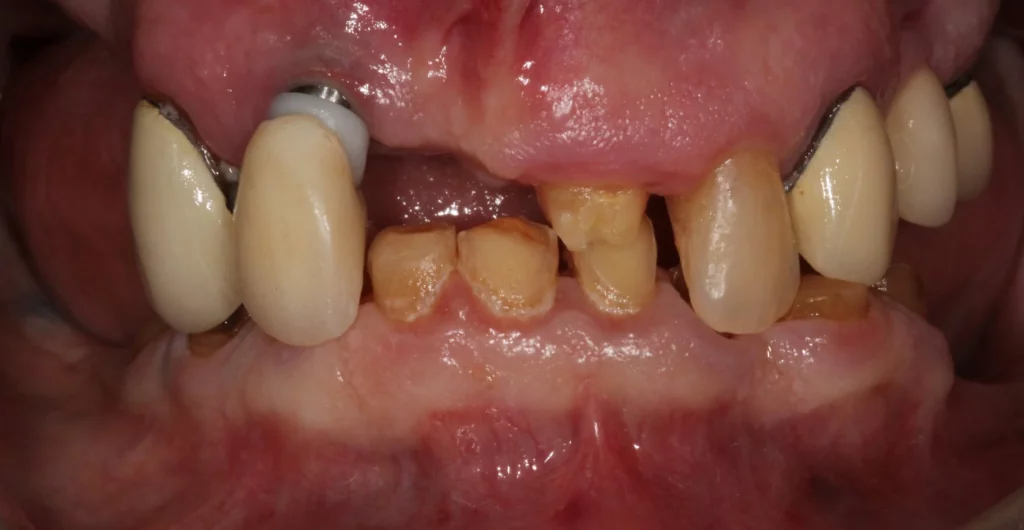

A dental bridge is a replacement for a missing tooth and is anchored to either the patient’s natural teeth, dental crowns, or implants. Dental bridges can also replace multiple missing teeth. They literally “bridge” the gap created by one or more missing teeth.

The drawback of a this approach is you have to remove some of the adjacent teeth (unless you want to have a fixed implant bridge).

An implant-retained crown on either side with false tooth in middle.

A Fixed Implant Bridge is a good option if you don’t want to change the good teeth around your missing tooth. You can see an example of this at the top of this page.